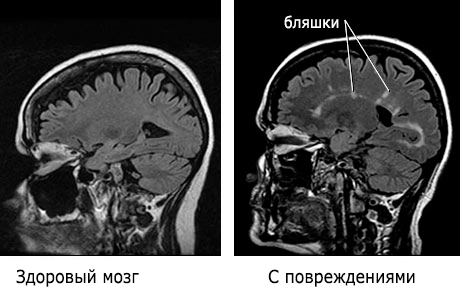

МРТ головного мозга при рассеянном склерозе. Выявляются множественные разнообразных размеров и форм очаги в белом веществе полушарий головного мозга.